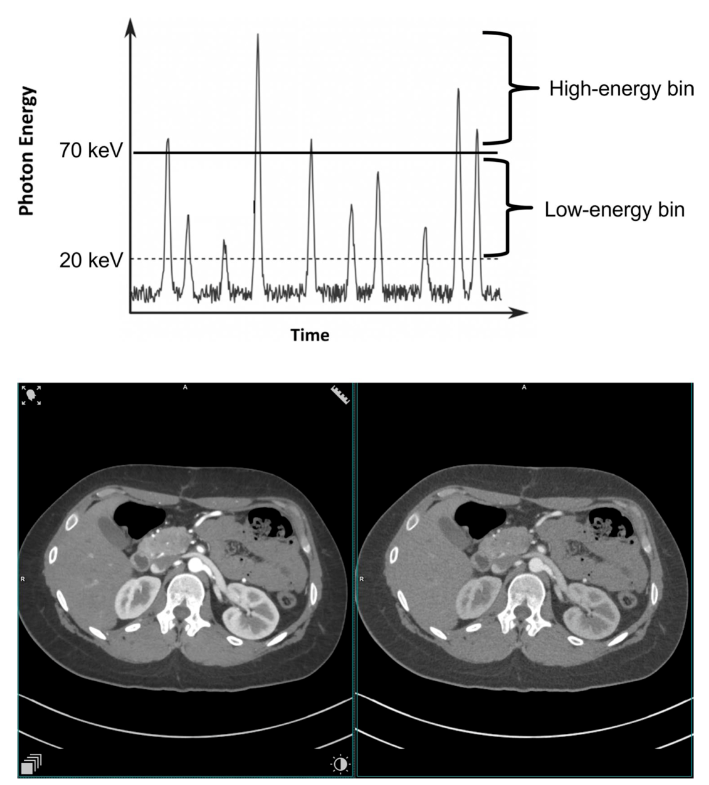

能量分辨PCD可使用多个阈值能量。图2展示了同时采集两个测量信号的过程,其中检测到的量子能量超过了阈值T0和T1。将相邻能量阈值的探测器信号相减,就会产生"能量仓"数据,其中包含能量在两个阈值之间的所有X射线计数。对CT数据进行能量分辨测量,可在任何CT扫描中进行多能量材料分辨。所有已建立的双能量应用都可以使用两个能量仓。使用三个或更多能量仓采集数据可区分两种造影剂(碘和另一种K-edge大于40 keV的材料,如钆或金)。

图2 在两个阈值能量(T0=20 keV,T1=70 keV)下采集数据的示意图,提供两个光谱分辨探测器信号。下图是一名25岁女性的腹部增强扫描图,该扫描图是用临床光子计数CT原型机在上述两个阈值能量下获得的